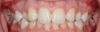

A third risk of using an implant to replace a missing lateral incisor is the continued vertical growth of the alveolar bone and eruption of the teeth adjacent to the implant.9,10 Traditionally, it has been taught that an implant can be safely placed when alveolar bone growth is confirmed complete with serial radiographs. However, numerous studies call that rule into question.11-16 Bernard et al evaluated vertical changes in teeth adjacent to implants in a young group of patients (15.5 to 21 years) and in a mature group (40 to 55 years), over a mean time of 4.2 years.17 In the young group, infraocclusion of the implant crowns ranged from 0.1 mm to 1.65 mm, while in the mature group the infraocclusion of the implant crowns ranged from 0.12 mm to 1.86 mm. An example of infraocclusion that occurred in a young implant patient over time is depicted in Figure 3 and Figure 4. Based on classic literature as cited here, it seems prudent to delay the placement of implants in high-risk areas, such as the maxillary lateral incisor region, for as long as possible or perhaps avoid it altogether.

Fig 3. Implants were placed in a 20-year-old female patient in the Nos. 7 and 11 sites with a pontic replacing No. 10.

Fig 4. A 15-year postoperative photograph of the patient in Fig 3 illustrates the significant infraocclusion of the implants compared to the natural teeth. Also, note the blue tissue discoloration over implants Nos. 7 and 11.